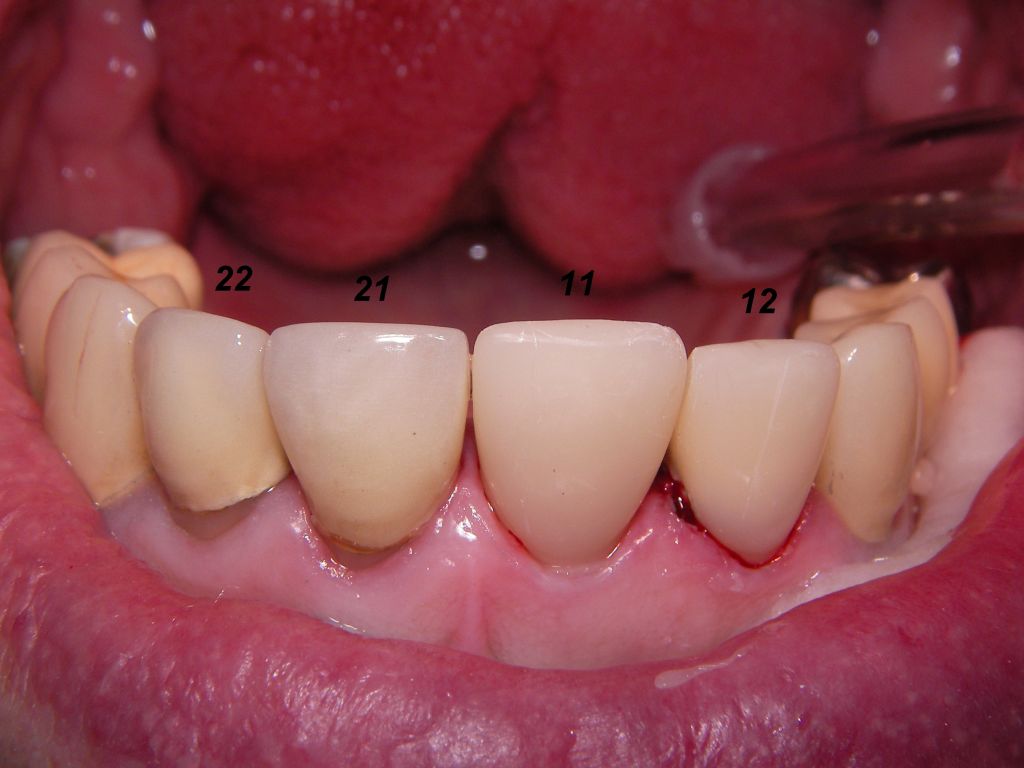

Links das Kontrollfoto nach der Sitzung am 17.2.06. Damit war die Vorbehandlung in diesem Fall abgeschlossen. | |

Am 28.2.06 erfolgte die endgültige Präparation (das "Beschleifen") aller 4 Zähne. Links das Modell, auf dem die Kronen gefertigt worden waren. Rechts kurz vorm Zementieren der Kronen am 13.3.06. Aus der Längendifferenz der Zähne rechts und links kann man darauf schließen, daß die Präparation tief unter dem Zahnfleisch erfolgen mußte. |

Links die Kronen aus dem Dentallabor "Heitmeyer Zahntechnik", Osnabrück. Man sieht praktisch keinen Metallrand. Der Patient war zur Farbbestimmung im Dentallabor - so halten wir es praktisch immer. Rechts das Ergebnis bei der 1. Nachkontrolle am 27.3.05. Das Zahnfleisch muß sich noch etwas erholen. |